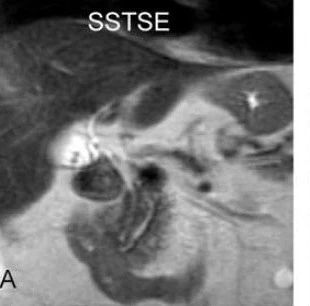

想读懂胆囊及胆管结石MRI表现?快看看这篇文章!